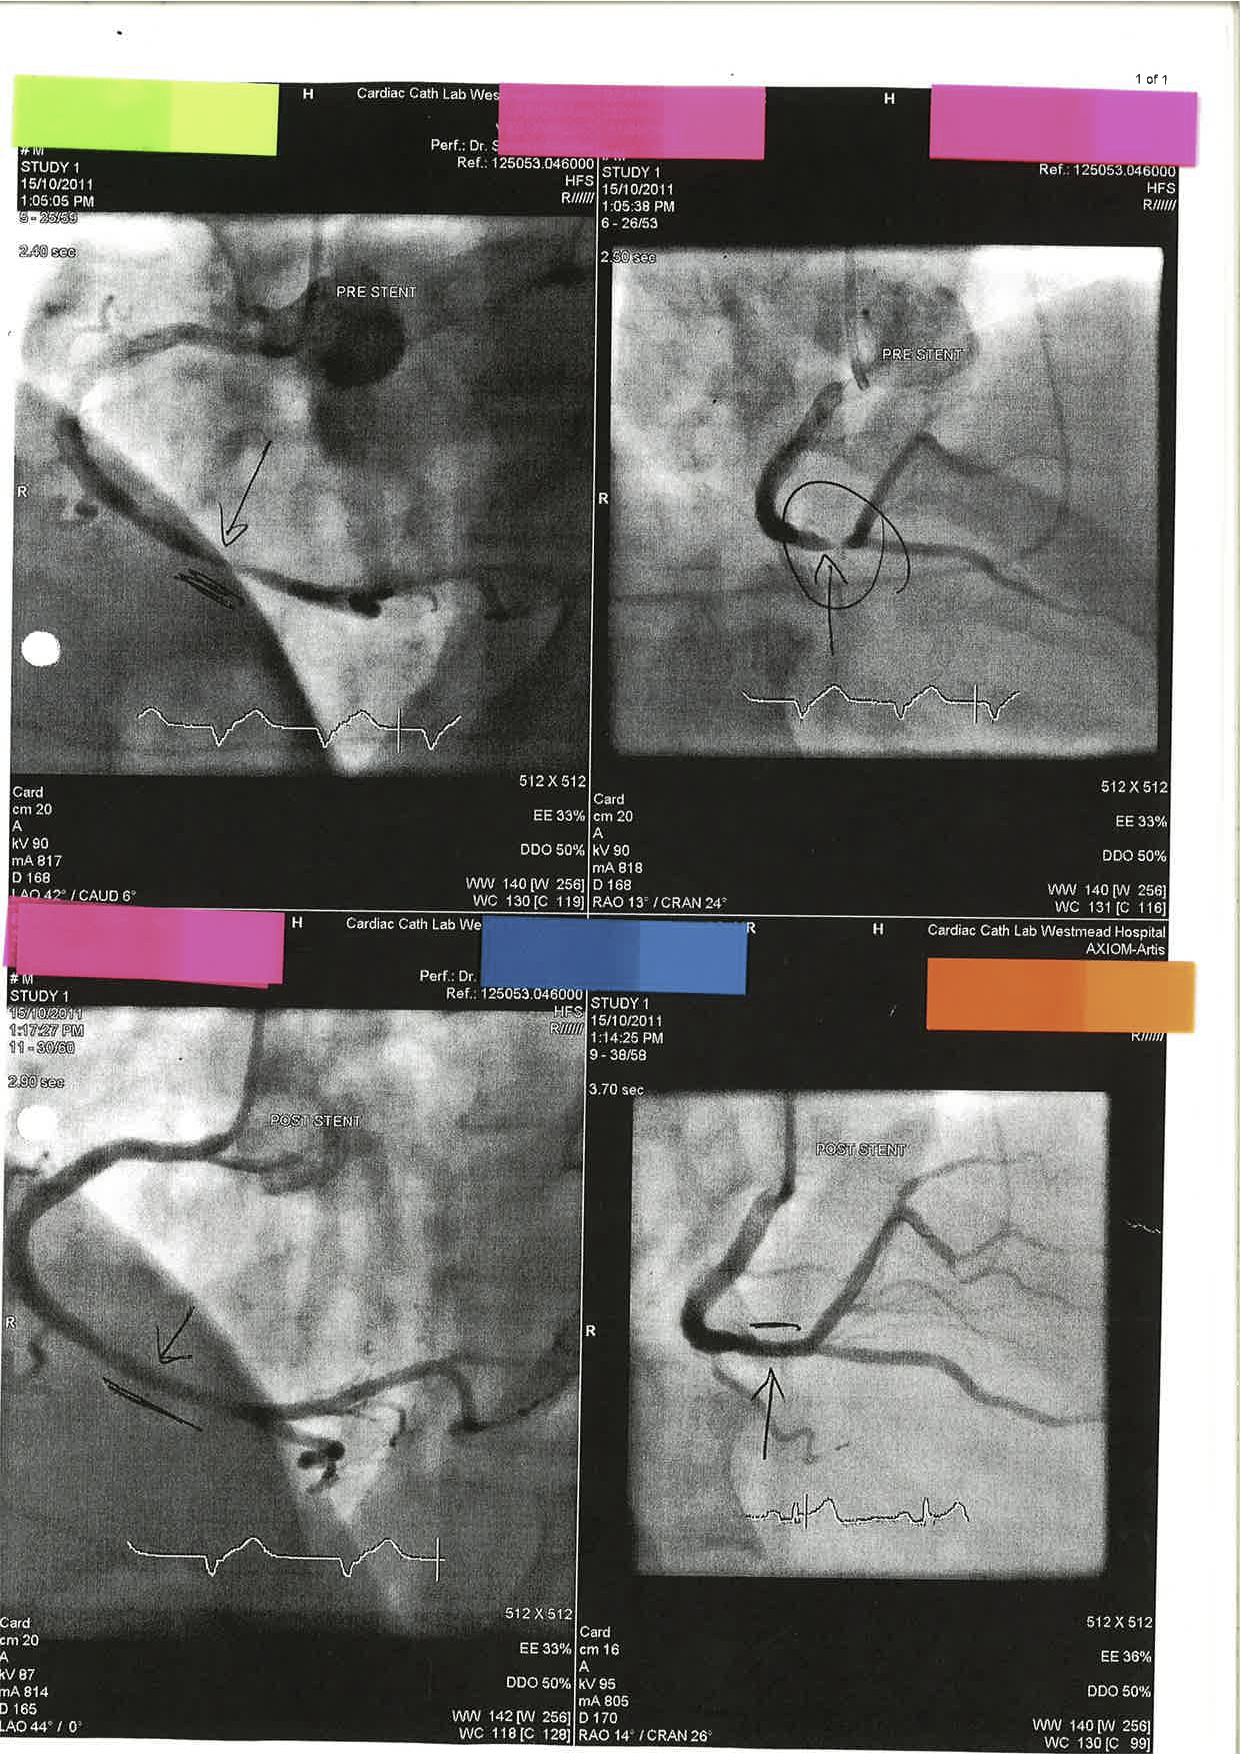

ECG 10 – A 64 year old man with Acute Onset of Chest Pain

ECG 10 (above) shows inferior ST elevation (III, II and aVF) with reciprocal ST depression in aVL. There are no specifc features of a Right Ventricular Infarction. The patient is sent to the Cardiac Catheter Lab and has the following findings: